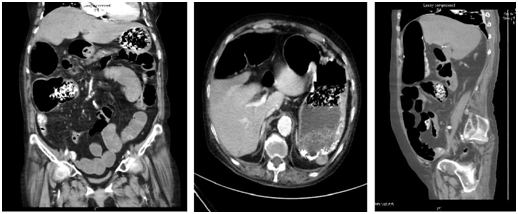

A 76year old Chinese female with multiple co-morbidities was admitted after a fall while sustaining a stable head injury. Her past medical history includes hypertension, dyslipidemia, ischemic heart disease with a history of angioplasty and ejection fraction of 30% and moderate mitral regurgitation, end-stage renal failure on hemodialysis, gout, asthma, previous sigmoid cancer with left hemicolectomy 2years ago and recurrent falls. After a few days of observation in the hospital, while waiting to be discharged from hospital to a step-down care at community hospital after, she suddenly presented with right sided abdominal pain. The pain was associated with two episodes of non-bloody, non-bilious vomiting and abdominal distension. Upon physical examination, she was hypotensive, with cold clammy extremities. Her abdomen was mildly distended, with generalized tenderness and guarding especially over the right side. The laboratory investigation shows a high white blood count of 16.95 with normochromic and normocytic anemia, as well as a raised lactate level of 3.5 and metabolic acidosis on the arterial blood gas panel (pH 7.36 pCO2 37.8 pO2 37.8 pO2 183.8 Base Excess -4.3 Bicarbonate 20.9). C-Reactive protein (CRP) level was 333. Acute intestinal obstruction was suspected and a supine abdominal X-ray (AXR) was done immediately which showed multiple gas-filled prominent loops of bowel (Figure 1).

Figure 1 AXR showing dilated bowels.